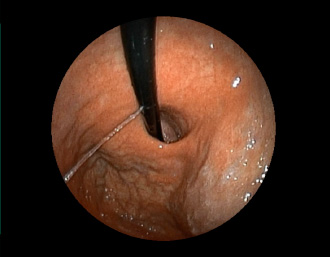

症例1:胃潰瘍(37才、男性)

①胃潰瘍(Stage A1)

健診:胃レントゲン検査で、胃角部ニッシェを指摘され当院受診。

胃角部小弯に、深くて大きな、大きさ約10mmの胃潰瘍(stage 1)

があり、潰瘍底は一部白苔はみ出しを認める。エソメプラゾールマグネシウム水和物投薬で治療開始しました。

(インジゴカルミン散布画像)